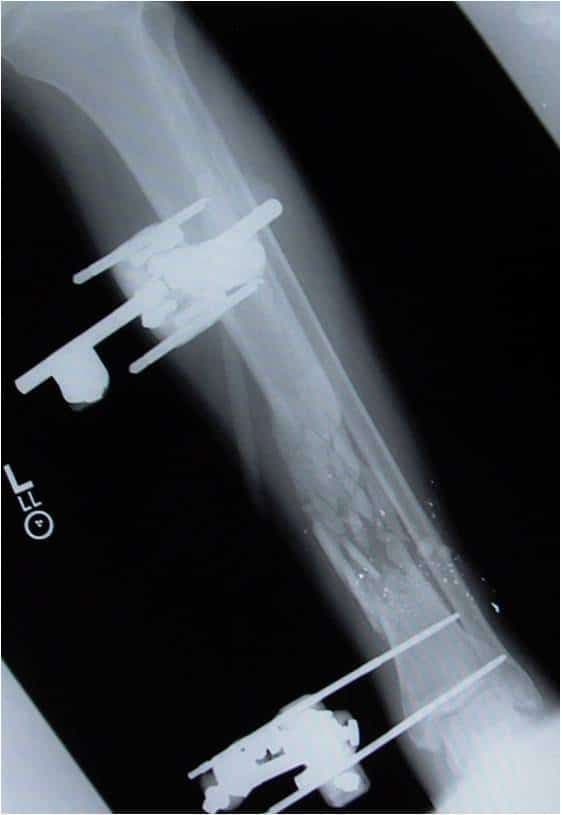

2. Уникайте встановлення штифта занадто близько до місця перелому (штифти всередині самого перелому зменшать здатність зовнішнього фіксатора підтримувати стабільність перелому) (зобр. 2 і зобр. 3. Рентгенологічний знімок цієї гомілки у прямій проекції передбачає адекватне розміщення зовнішнього фіксатора, проте на бічному знімку видно, що проксимальний штифт дистальної групи штифтів знаходиться всередині перелому).

Зобр. 2

Зобр. 3

1. див. зобр. 8. Переднезадня рентгенограма встановлення зовнішнього фіксатора з приводу перелому великогомілкової кістки.

Зобр. 8